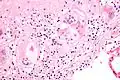

Cuerpo de asteroide en sarcoidosis.